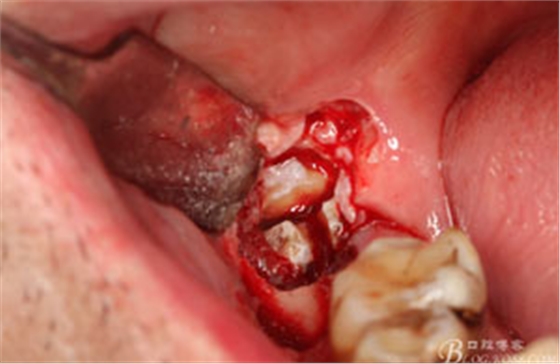

圖12. 先取出48牙冠

圖13.從頰側(cè)和舌側(cè)兩個(gè)方向用挺。挺出牙根